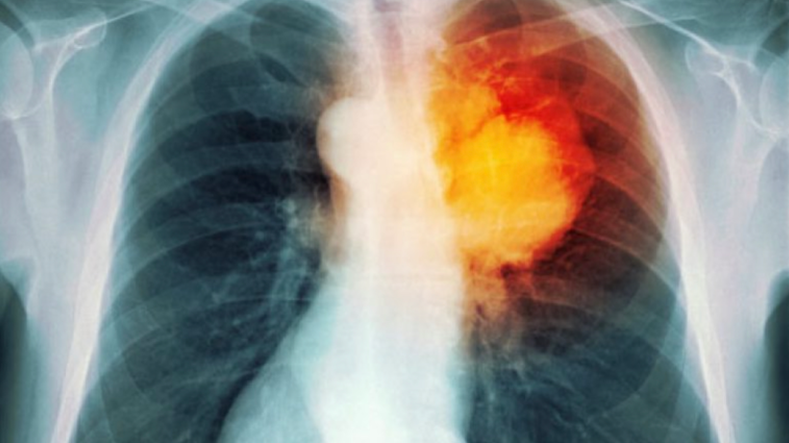

Pa mushkëritë nuk ka jetë. Ato janë të nevojshme për pastrimin e oksigjenit nga toksinat dhe transportimin e tij nëpërmjet gja kut drejt të gjithë organizmit.

Sistemi i frymëmarrjes duhet mbrojtur me fanatizëm për një jetë më të gjatë. Mbrojtja fillon duke u kujdesur në ushqimet, pijet dhe substancat që lejojmë të futen në organizëm. Në këtë artikull do të mësoni për ushqimet dhe pijet më të domosdoshme për shëndetin e mushkërive.